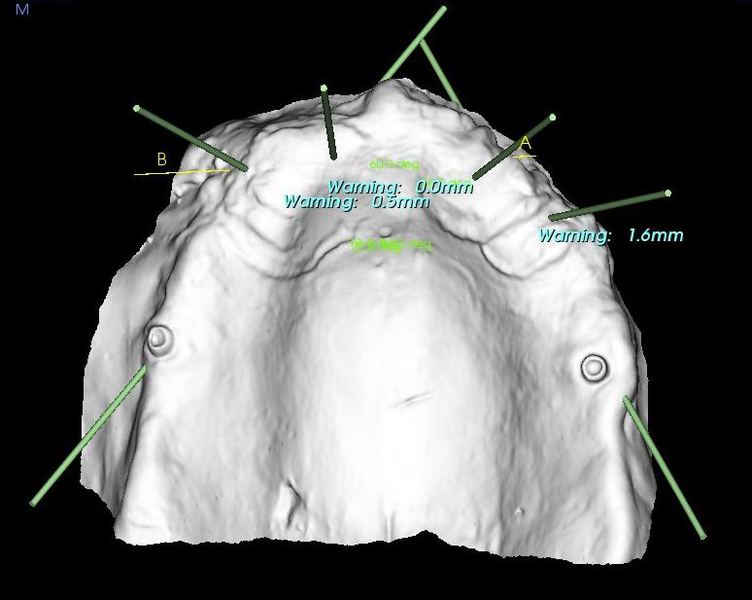

The CT scanner's imaging allows us to create custom made surgical guides specific to each patient.  These surgical guides allow the precise placement of dental implants for optimal functional and esthetic results.

CT Guided Custom Implant Placment